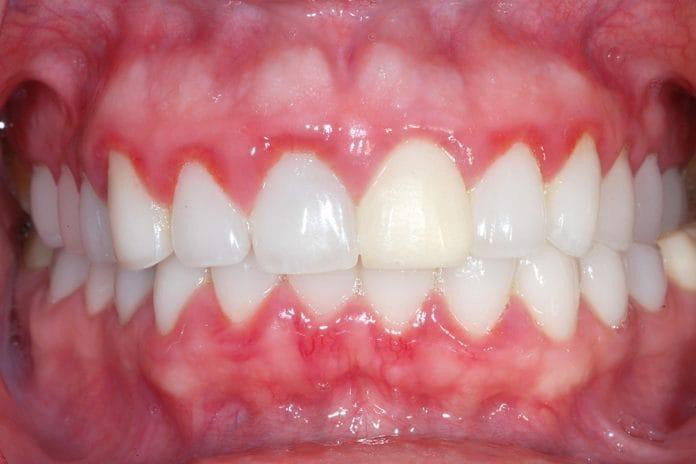

1. Gingivitis (Gambar 2) Gingivitis merupakan inflamasi terbatas pada jaringan gingiva tanpa kehilangan perlekatan klinis, sedangkan periodontitis ditandai oleh kehilangan perlekatan jaringan, pembentukan poket periodontal, dan resorpsi tulang alveolar1,4,5,6.

Gambar 2. Gingivitis (Peradangan pada gusi)4